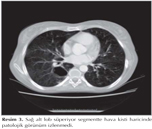

Otuz ?? ya??nda kad?n hasta ciddi epistaksis nedeniyle acil servise ba?vurdu. Konv?lziyon ge?iren ve fazla miktarda kanaman?n akci?ere aspirasyonu sonucu akut solunum yetmezli?i geli?en olgu ent?be edilerek invaziv mekanik ventilat?r deste?i ba?land?. Yo?un bak?m ?nitesinde yap?lan de?erlendirmesinde hastan?n b?brek fonksiyon testlerinin ileri derecede bozulmu? oldu?u g?r?lerek hemodiyaliz tedavisi ba?land?. Olgunun ?z ge?mi?inde b?brek fonksiyon bozuklu?u nedeniyle b?brek biyopsisiyle fokal sklerozan glomer?lonefrit tan?s? ald??? ve yakla??k alt? ayd?r sistemik steroid (40 mg metilprednizolon) ve siklosporin kulland??? ??renildi. Hemodiyaliz tedavisinin ikinci g?n?nde femoral vene tak?lan kateterde akut tromboz olmas? ?zerine ?ekilen BT anjiyoda sol ana iliyak ven bifurkasyon ?ncesinde, internal iliyak ven proksimalinde, eksternal iliyak vende de?i?ik derecelerde dolum defekti izlenen olguya d???k molek?ler a??rl?kl? heparin (DMAH) tedavisi ba?land?. Akci?er grafisinde sa?da orta zonda ve solda ?st zonda infiltrasyonlar izlendi. ?ekilen toraks BT'sinde her iki akci?erde ?o?u kaviter ?zellikte nod?l ve konsolidasyonlar, akci?er alt lobda apse ile uyumlu olabilecek lezyon g?r?ld? (Resim 1). Ay?r?c? tan?da ?ncelikle septik emboli d???n?len olguya ampirik antibiyotik tedavisi ba?land?. Tedavisinin be?inci g?n?nde ekst?be edilen hasta ileri tetkik ve tedavi i?in klini?imiz yo?un bak?m ?nitesine al?nd?. Olgunun fizik muayenesinde vital bulgular? normal s?n?rlarda izlendi. Olgunun mukozalar? soluktu ve ciltte burun ?zerinde ve a??z kenarlar?nda telanjiektaziler g?r?ld?. Solunum sistemi muayenesinde bilateral ince raller duyuldu. Kalp muayenesinde ?f?r?m duyulmad?. ?z ge?mi?i sorguland???nda tekrarlayan abortus ?yk?s? oldu?u ??renildi. Ald??? antibiyotik, DMAH ve steroid tedavisine devam edilen olguda epistaksis tekrarlad?. DMAH tedavisi kesildi. Tedaviye ra?men kanamas? durmayan ve tampon de?i?tirilmesi s?ras?nda kanamas? artarak asfiksi geli?en hasta yeniden ent?be edilerek mekanik ventilat?re ba?land?. Kontrol akci?er grafisinde sol akci?erde totale yak?n atelektazi izlendi. Endotrakeal t?p yoluyla fiberoptik bronkoskopi ile de?erlendirildi. Trakea alt ucundan kaynaklanan ve sa? ve sol ana bron?lar? obstr?kte eden ve bronkoskopun ilerlemesini engelleyen lezyon saptand?. G???s cerrahisi ile kons?lte edilerek rijid bronkoskopisi yap?ld? ve kitlesel lezyon eksize edildi (Resim 2). Bron? lavaj patoloji sonucu fibrin ve mantar elemanlar? olarak raporland?. ?ntraven?z kaspofungin tedaviye eklendi. Kontrol akci?er grafisinde atelektazinin d?zeldi?i izlendi. Yo?un bak?m izleminde hematokezya geli?ti. Sistemik steroid tedavisi kesildi. Kanama profili normal izlendi. ?zlemde kanamas? olmayan hastaya ek cerrahi giri?im d???n?lmedi. Yo?un bak?m yat???n?n alt?nc? g?n?nde ate? y?ksekli?inin devam etmesi sebebiyle tedaviye teikoplanin eklendi. ?zlemde mekanik ventilasyonda spontan modda takibe al?nan ard?ndan T t?p ile oksijen deste?i alt?nda izlenen hastan?n sat?rasyonlar?nda d??me olmamas? ve hemodinamisinin de stabil seyretmesi ?zerine yo?un bak?m yat???n?n 14. g?n? ekst?be edildi. Ate? y?ksekli?i, oryantasyon, kooperasyon bozuklu?u olmas? ve konu?amama ?ikayetleri ile n?roloji taraf?ndan de?erlendirildi. Beyin MR'sinde sol insular korteks d?zeyinde akut iskemiye i?aret eden dif?zyon k?s?tlanmas? izlendi. Kanama zaman? in vitro trombosit fonksiyon testi (COL-EPI, PFA-100) ile de?erlendirilerek normal bulundu. Lupus antikoag?lan? negatif, antikardiyolipin antikor IgM ve IgG negatif, anti-β2-glikoprotein I IgM 5.6 MPL U/mL, IgG 8.4 GPL U/mL, IgA 6.0 U/mL olarak geldi. Di?er romatizmal mark?rlar? negatif gelen hastada primer antifosfolipid antikor sendromu (APS) d???n?lerek sistemik steroid tedavisi ba?land? (1). ?zleminde ate? yan?t? al?nd? ve klini?inde belirgin d?zelme izlendi. Kontrol toraks bilgisayarl? tomografisinde sa? alt lob s?periyor segmentte hava kisti haricinde patolojik g?r?n?m izlenmedi (Resim 3). Klinik ve radyolojik de?erlendirmede stabil olan hasta taburcu edildi.

Resim 3